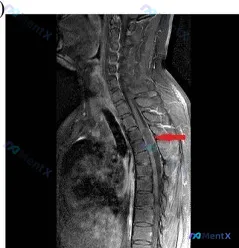

病例影像核心表现

- 序列与部位:胸椎矢状位MRI,中下段(约T6-T8水平)为主

- 关键阳性发现:

- 椎管内占位:可见增强的囊性肿块,伴硬膜囊明显受压,脊髓形态变扁

- 脊髓高危信号:受压节段脊髓实质内见T2高信号灶(提示水肿/缺血/软化)

- 椎体/骨髓异常:T6、T7椎体可见T2高信号区,提示骨髓水肿或病理性浸润

- 椎间盘退变:相应节段椎间盘信号普遍减低